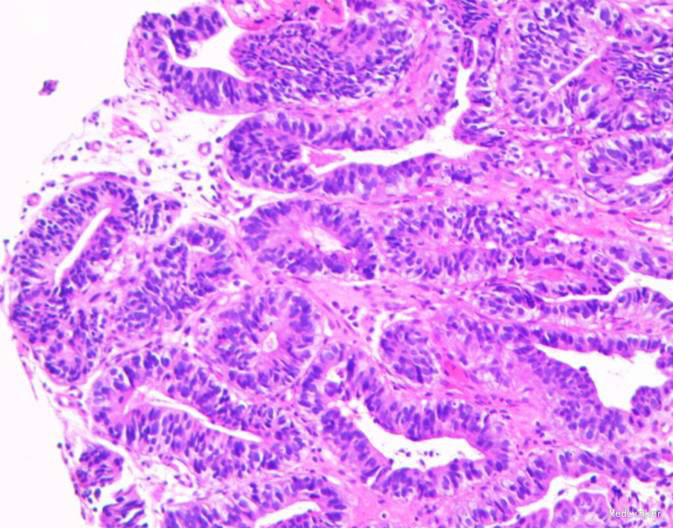

患者,男性,69岁,间歇性中上腹隐痛1月,加剧1周来我院门诊就诊,胃镜检查:见胃窦前壁处可见一1.5*2.0cm粘膜隆起,表面粗糙,见图1,胃镜诊断:胃窦粘膜隆起(性质待病理),慢性浅表性胃窦炎伴胆汁反流,10月26日门诊病理:胃窦:慢性萎缩性胃炎,急性活动,伴部分腺体中重度不典型增生,局灶重度不典型增生。于2015年10月28日入院。

随访:出院后2周,电话随访患者,一般情况良好,无不适主诉。 讨论:该患者胃镜见一胃窦前壁粘膜隆起,表面粘膜粗糙,病理示:慢性萎缩性胃炎,伴部分腺体中重度不典型增生,局灶重度不典型增生,超声胃镜病灶未突破粘膜下层,有胃ESD手术指征,故行全麻下胃ESD术。术后病理:胃窦前壁肿瘤:腺上皮高级别上皮同瘤,部分癌变,病变大小1.5*1.1*0.3cm,基底及切缘未见癌。说明手术成功,切缘及基底均无肿瘤侵及。对于早癌患者我们完全可以通过采用ESD方法治愈患者,胃镜下切除早癌较腹腔镜创伤更小。我和患者解释时是这样说的:腹腔镜是微创,而我们内镜下ESD则是微微创。